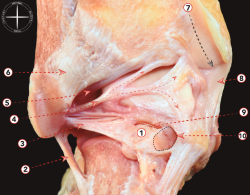

Esto tiene algunas implicaciones quirúrgicas, ya que permitirá la resección de osteofitos en la superficie anterior de la tibia o del astrágalo a través de una técnica artroscópica (Figura 1). También tiene un receso anterior, más evidente durante la flexión dorsal del tobillo, ya que la cápsula de la articulación del tobillo se tensa en la flexión plantar y se relaja en la flexión dorsal.

Figura 1. Visión lateral de una disección osteoarticular del tobillo, donde la cápsula anterior ha sido preservada e inyectada con aire. Esta imagen permite entender la creación de un espacio de trabajo anterior durante la artroscopia de tobillo. 1: ligamento talonavicular dorsal; 2: cápsula anterior del tobillo; 3: ligamento tibiofibular anterior; 4: cápsula posterior del tobillo; 5: tendón calcáneo.

Precisamente este detalle permite la creación de un área de trabajo durante la artroscopia de tobillo. El alto grado de congruencia de la articulación del tobillo dificulta la introducción de instrumentos en la articulación. Pero si el cirujano trabaja con el tobillo en posición dorsiflexionada, el receso de la cápsula anterior del tobillo se relaja y permite crear una área de trabajo anterior segura.